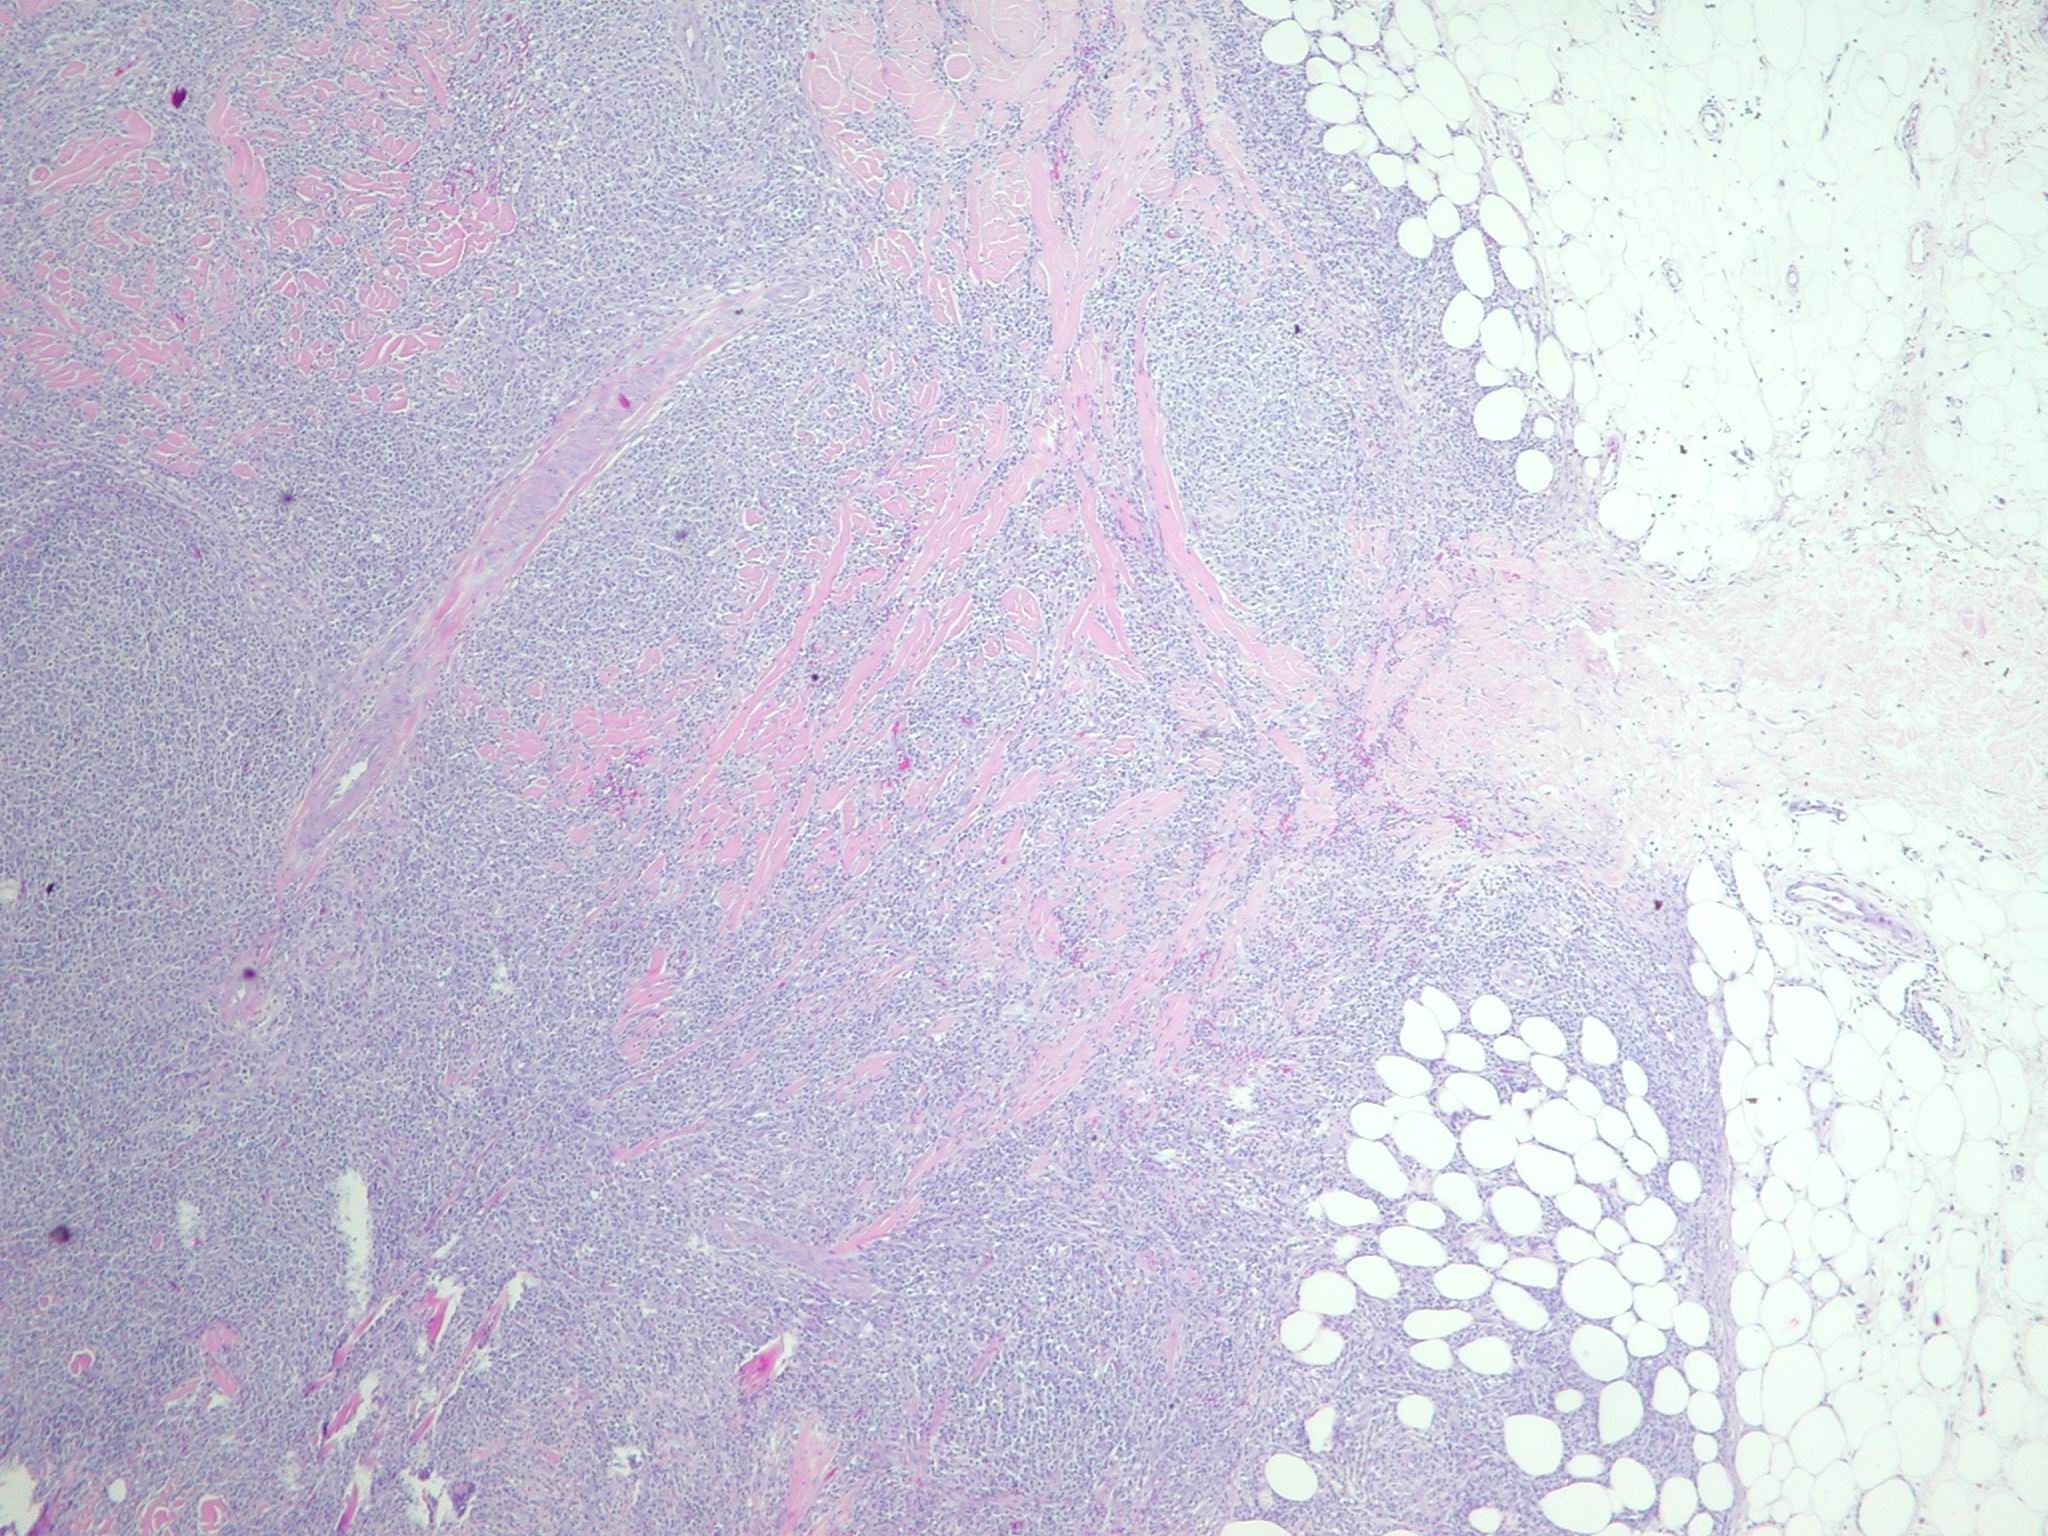

Anaplastic Large Cell lymphoma =لمفوما كبيرة الخلايا غير مصنعة